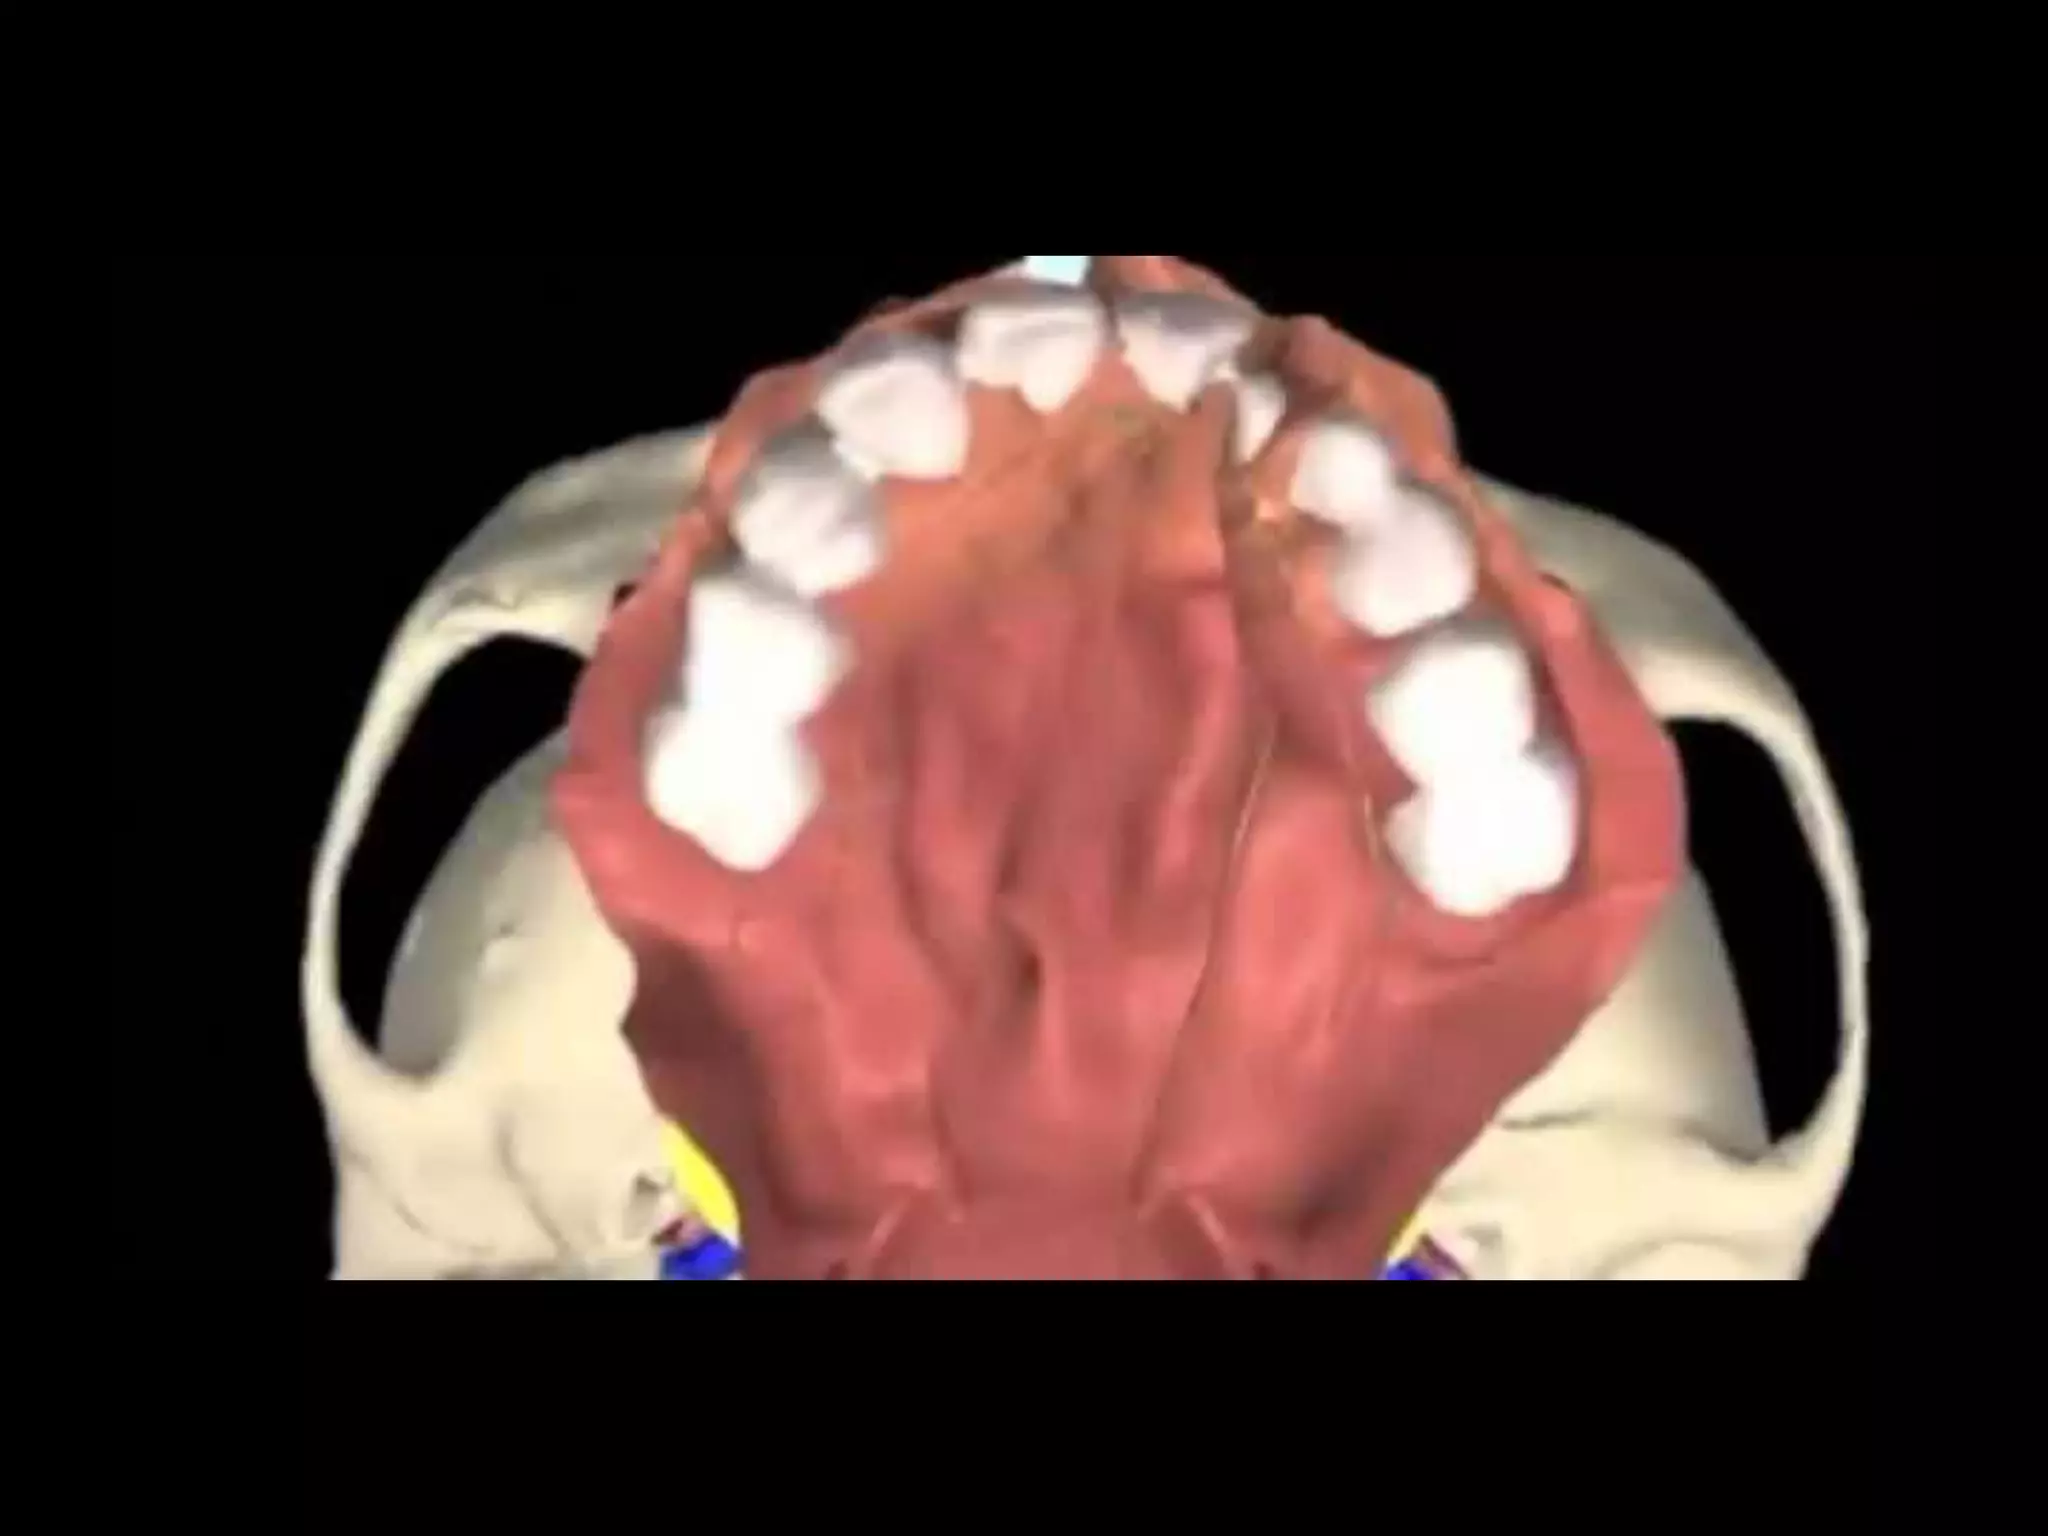

Classification

Classification  Nagpur classification ◦Group I – cleft lip only ◦ Group Ia – cleft lip + cleft alveolus ◦ Group II – cleft palate only ◦ Group III – cleft lip + cleft alveolus + cleft palate